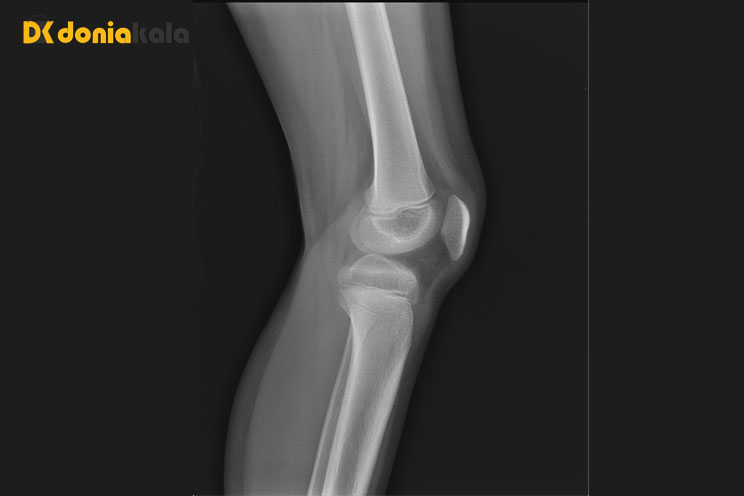

اشک Tears: پارگی چهار سر ران زمانی را توصیف می کند که تاندون به طور جزئی یا کامل قطع می شود. این آسیب مشابه یک فشار است اما شامل کشش بیش از حد و پارگی است. در برخی موارد، آسیب ممکن است به صورت پارگی جزئی در جایی که تاندون در حال ساییدگی است شروع شود، اما سپس پیشرفت کرده و باعث پارگی کامل تاندون می شود. این آسیب ممکن است باعث جدا شدن عضلات از کاسه زانو شود، به این معنی که فرد نمی تواند زانوی خود را صاف کند. یک فرد ممکن است پس از پارگی تاندون چهارسر ران خود، همراه با احساس درد و تورم، صدای ترکیدن را بشنود. آنها همچنین ممکن است متوجه شکافی در بالای کاسه زانو شوند که در آن تاندون پاره شده است. درمان ممکن است متفاوت باشد اما می تواند شامل استراحت، فیزیوتراپی و جراحی باشد.